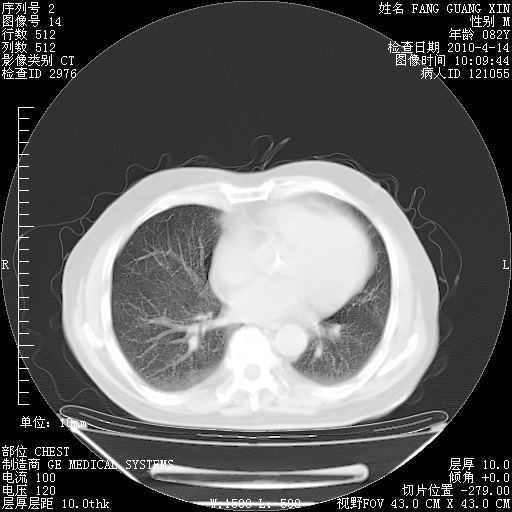

4月14日肺部CT

23.JPG

24.JPG

25.JPG

26.JPG